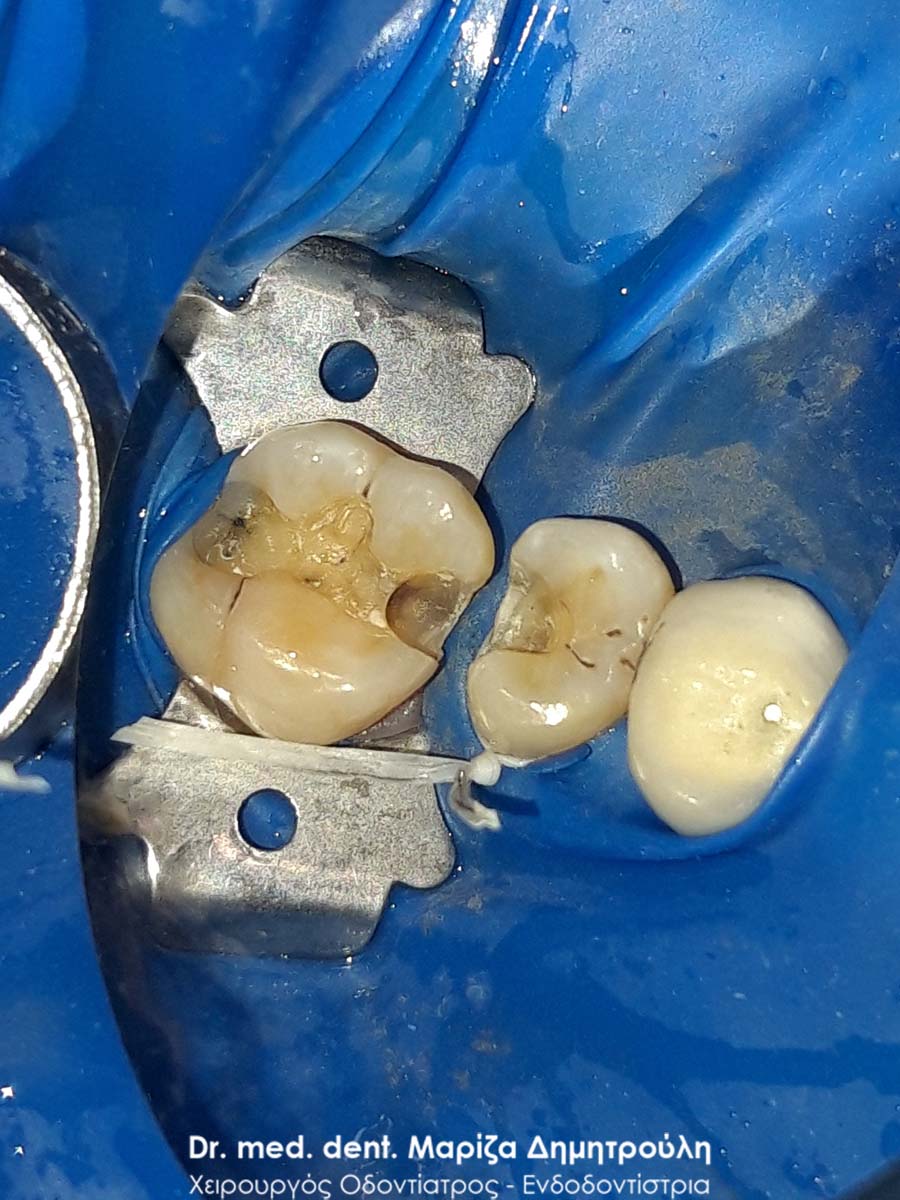

Περιστατικό – Αντικατάσταση σφραγισμάτων δοντιών

Ο ασθενής επιθυμούσε την αντικατάσταση των παλιών μαύρων σφραγισμάτων αμαλγάματος με λευκά σφραγίσματα σύνθετης ρητίνης.

Η θεραπεία πραγματοποιήθηκε με τη χρήση ελαστικού απομονωτήρα, όπως ορίζουν τα παγκόσμια πρωτόκολλα οδοντιατρικής για την αφαίρεση των μαύρων σφραγισμάτων. Οι οδοντίατροι θα ήταν καλό να χρησιμοποιούν απομονωτήτρα κατά την αφαίρεση σφραγισμάτων αμαλγάματος, έτσι ώστε ο ασθενής να εισπνέει ελάχιστα και να μην καταπίνει τον υδράργυρο, που απελευθερώνεται κατά τη διαδικασία αυτή.

Το σχέδιο θεραπείας του πρώτου γομφίου (δόντι με πολύ λευκό σφράγισμα) ήταν υπό συζήτηση, γι΄ αυτό και η αποκατάσταση του δοντιού με προσωρινό σφράγισμα.

ΠΡΙΝ

META